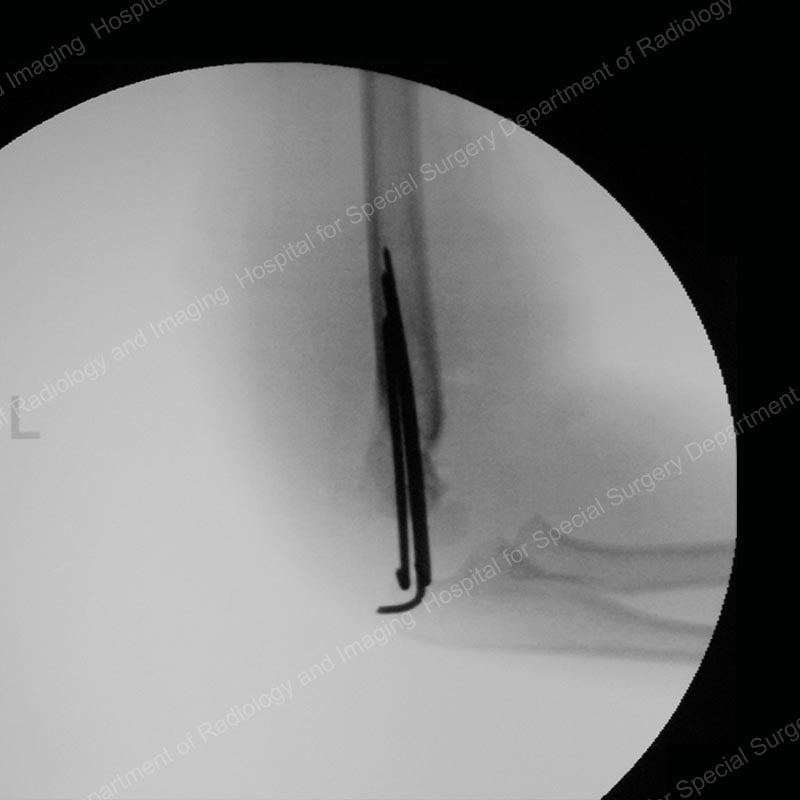

To repair a supracondylar fracture, the orthopedic surgeon realigns the bone and usually inserts wires – about the diameter of a pencil lead – into the bone and across the fracture site, an approach that helps maintain proper alignment while protecting the growth plate in these young children. The wires extend through the skin and are covered by the cast.

Figure 2: Lateral (side) X-ray of a supracondylar humerus fracture after treatment with realignment and wiring.